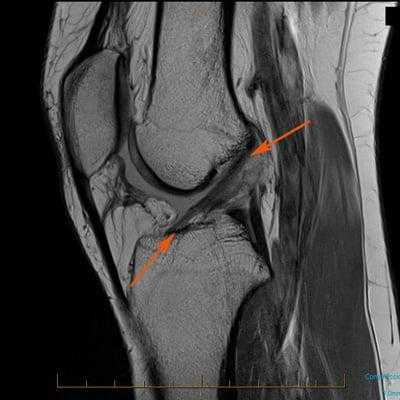

Нарушение целостности, а именно ее разрывы, преимущественно происходят на почве спортивных травм, а также в результате падений с зафиксированными параллельно поверхности ногами (травма лыжников), неудачных приземлений после прыжка на выпрямленные ноги. Поражение связочных пучков также может возникнуть из-за сильного удара с тыльной стороны колена, скручивающих и резких движений, например, при крутом повороте или резком торможении в момент бега. Распознать, что произошло поражение именно данной связки, можно только посредством определенных средств диагностики:

- МРТ (КТ и рентген менее эффективны);

Как травма выглядит на МРТ.